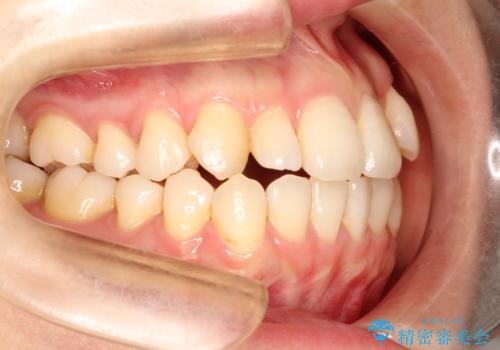

インビザラインで八重歯の矯正

- 八重歯を治したいとのことで、来院されました。

インビザラインにて、上顎の歯と歯の間をわずかに削り、並べる計画としました。